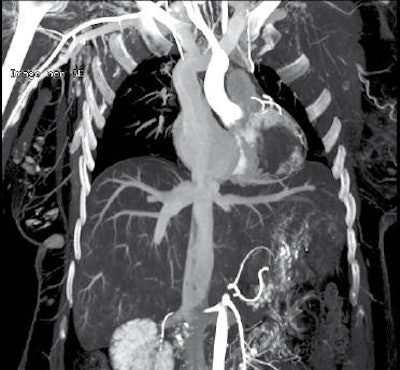

Virtual autopsy can be defined as one that takes place without dissecting a body thanks to a combination of various imaging techniques, including MRI and CT. The idea of combining medical imaging with forensic investigations came from Dr. Gil Brogdon of the University of South Alabama (who died in March 2014), but the first thanatological use of the scanner comes from the Bern Institute of Forensic Medicine in Switzerland.

According to its creator, Dr. Michael Thali, the neologism "virtopsy" is a combination of virtual (from the Latin virtualis) and autopsy, and it means carrying out a virtual autopsy without recourse to the scalpel. It also involves improving the quality of data acquisition in forensic medicine (virtualis: usable, industrial, improved). Where the autopsy offers a "view of oneself," the virtopsy acts in a complementary way to give a "better view" and guide the autopsy.

It offers the option of gathering information from the whole body more quickly, and of studying those areas that are difficult or even impossible to access during traditional autopsies, and thus to carry out an autopsy directly on the areas of interest. This speed of operation could, for example, be used in rapid identification in cases of mass disaster.

CT scanning also proves advantageous in the study of bodies that are in a state of putrefaction (recovered long after death, or after several days in the sea), carbonized, or in a skeletal state, especially with the aim of identifying the person and searching for projectiles and skeletal fractures forming part of injuries caused by a third party.